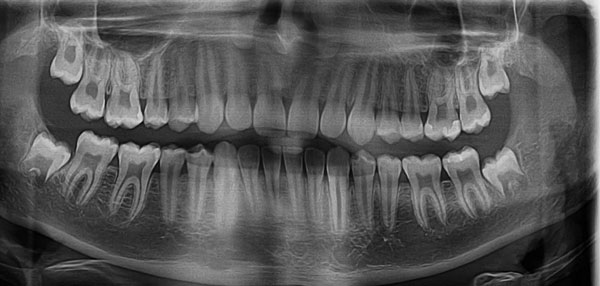

DIGITAL X-RAYS

(PANORAMIC DIGITAL X-RAY)

Digital x-rays offer improved imaging with less radiation to our patients than conventional x-rays. Digital x-rays have wider range of viewing options to catch problems earlier. Early detection usually means more conservative treatment and consequently better oral health. Being able to educate and explain problems with visual aid is a tremendous benefit to the patient and doctor alike.